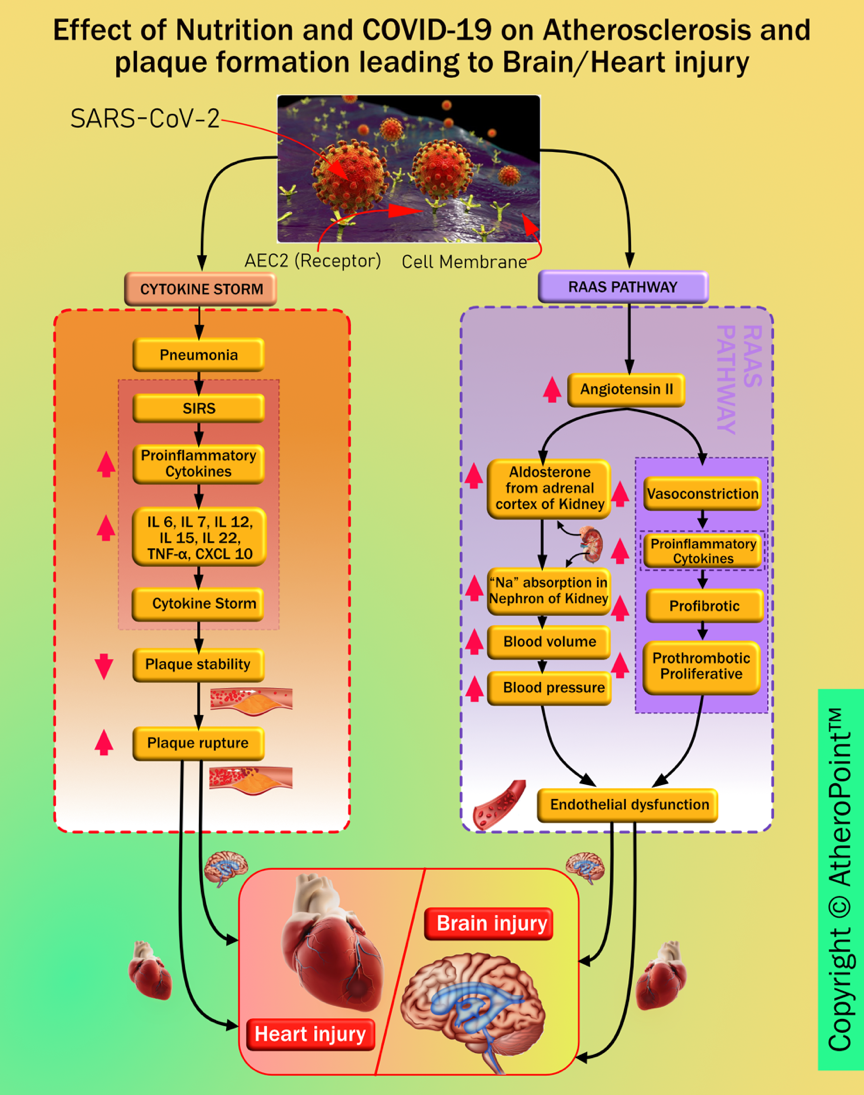

Imaging has shown to be very useful in understanding COVID-19 severity [241, 242]. Comorbidity has been shown to affect the lungs and heart more aggressively [45, 46, 49]. SARS-CoV-2 causes brain and heart injuries via different pathways (as seen in Fig. 11).

Fig. 11.

Fig. 11.Pathways linking COVID-19 to heart and brain injury.

Trends have shown a worsening of cardiac events in COVID-19 patients with underlying conditions such as coronary artery disease, hypertension, and diabetes mellitus [266]. Many reports from admitted patients have also suggested cardiac injury in about 12% to 26% of them. This exists due to the presence of pericytes in the heart, which have a high expression of ACE2 that are the same receptors through which the virus gains entry into the cells of the body. The cytokine released during the infection could affect the intramural coronary vessels of the patients. It is also seen that cardiovascular diseases have a major effect on ARDS in patients with COVID-19 affected lungs [239].

Some studies also suggest that abnormal immune system response is likely to be the underlying cause of myocardial injury during coronavirus infection. Thus, it is suggested that potential cardiac involvement should be identified early to provide a prompt diagnosis for improving the outcome [45]. It is noted that the consequences of dysregulation of the renin-angiotensin system caused by SARS-CoV-2 inside atherosclerotic plaques lead to endothelial dysfunction. This progresses into thrombosis, which in turn favours the invasion of plaque by inflammatory cells. These events may transform vulnerable plaque into a complicated and ruptured plaque [267]. Some studies also suggest that if positive for SARS-CoV-2 and asymptomatic, patients could be at increased risk of developing cerebral ischemic strokes, and myocardial infarction due to increased instability of coronary and carotid plaques [49, 268].

As mentioned above COVID-19 patients develop several complications, among these is the elevated level of IL-6 (interleukin-6). It is responsible for signalling the liver to increase the synthesis and secretion of C-reactive protein (CRP) levels [269]. Higher CRP levels in the blood are diagnostic of extensive tissue damage and pathological inflammatory response. It was observed that at the early stage of COVID-19, CRP levels were positively correlated with the diameter of lung lesions and the severity of COVID-19 [270]. Moreover, CRP levels can be measured and used as a lab-based blood biomarker, which is a simple, affordable, and rapid way to assist the therapeutic conditions and to evaluate the severity of the disease [269]. Thus, CRP levels are also seen to be an effective diagnostic tool in measuring the severity of COVID-19. Anti-inflammatory agents helped in suppressing the elevated levels of IL-6, thus keeping CRP levels in check. In patients with CVD risk, a high burden of subclinical inflammation is associated with COVID-19 development of subclinical disorders or cause cardiovascular damage [271]. However, nonsteroidal anti-inflammatory drugs (NSAID) should be avoided in patients with a high risk of cardiovascular disease as they are seen to increase the risk of heart attack, stroke and high blood pressure [272, 273]. Generally, ACE2 plays an important role in the cellular entry of SARS-CoV2. Additionally, it also affects the renin-angiotensin-aldosterone system (RAAS), which acts as a central mechanism of many drugs including NSAIDs [B7]. An important study also shows the increase of expression of ACE2 levels on heart tissue of diabetic rats after treating with NSAIDs [274].